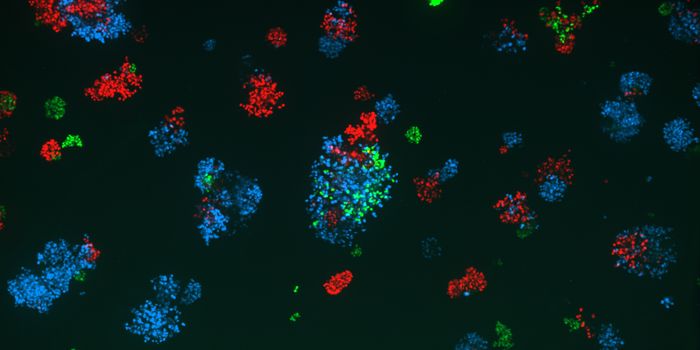

AUG 25, 2025CancerImmune checkpoint inhibitors (ICIs) have revolutionized the field of cancer immuno-oncology. ICIs act on cancer ce ...

JUN 12, 2025ImmunologyChemotherapy is a toxic form of cancer treatment that specifically dysregulates tumor cells and effectively mitigates tu ...